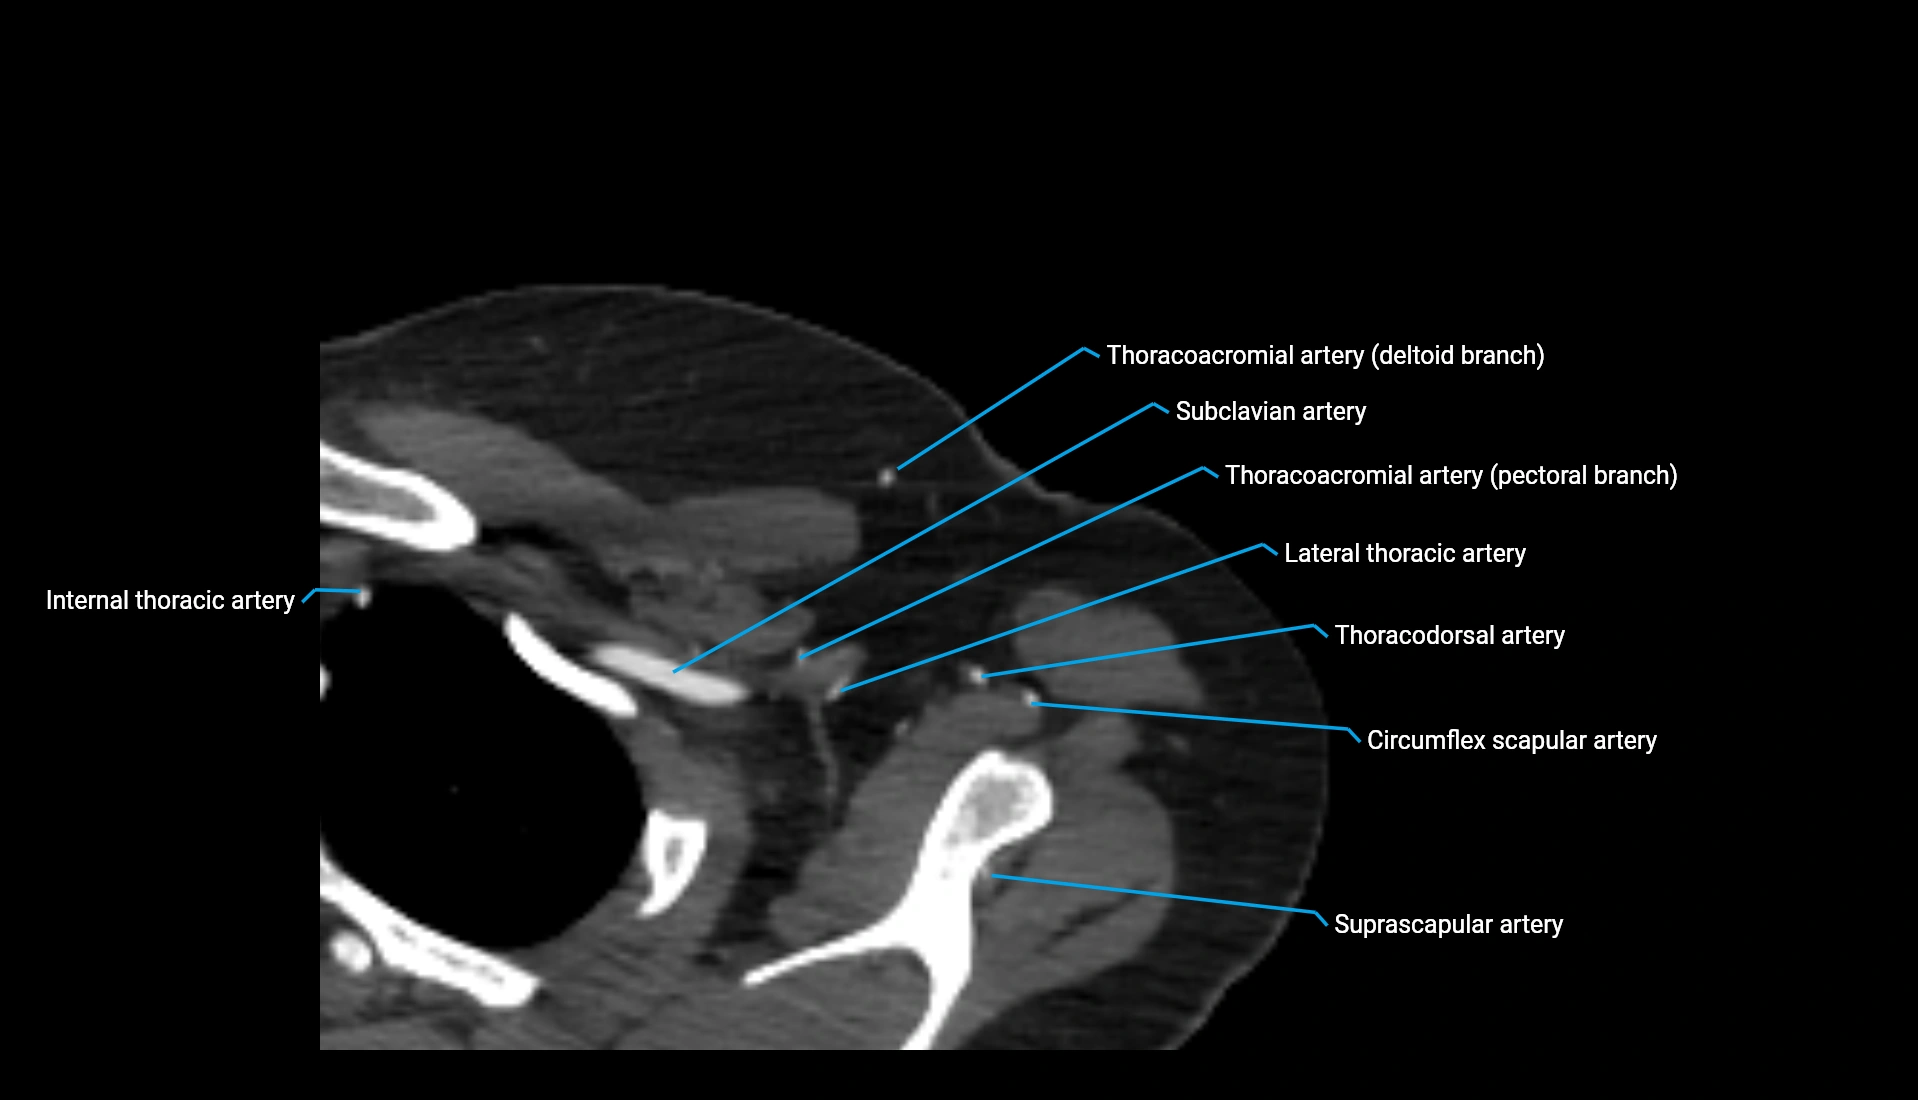

CT Appearance

Non-Contrast CT:

• Cortex: High-density, sharply defined

• Subchondral bone: Dense cancellous matrix

• Articular surface: Smooth concave contour articulating with the capitellum

• Excellent for evaluating bone integrity, alignment, and subtle fractures

Post-Contrast CT:

• Bone: No enhancement

• Joint capsule and synovium: Mild enhancement outlining the joint

• Improves contrast between soft tissues and bony margins

• Useful in detecting subtle joint abnormalities or postoperative changes